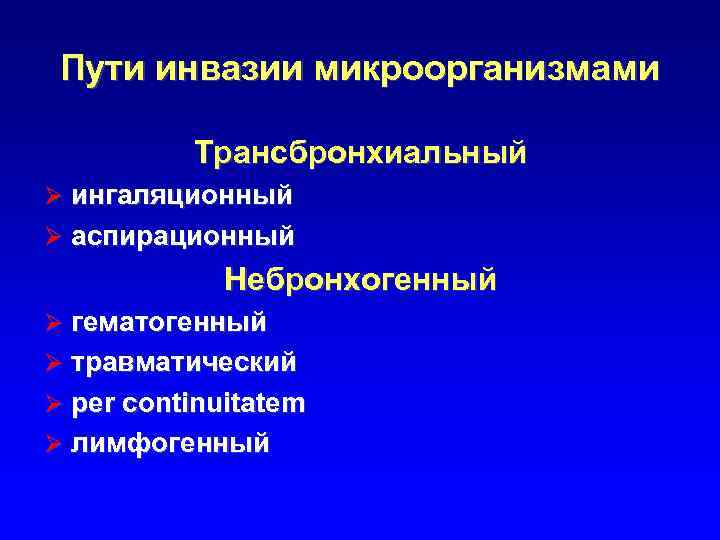

Пути инвазии микроорганизмами Трансбронхиальный Ø ингаляционный Ø аспирационный Небронхогенный Ø гематогенный Ø травматический Ø per continuitatem Ø лимфогенный